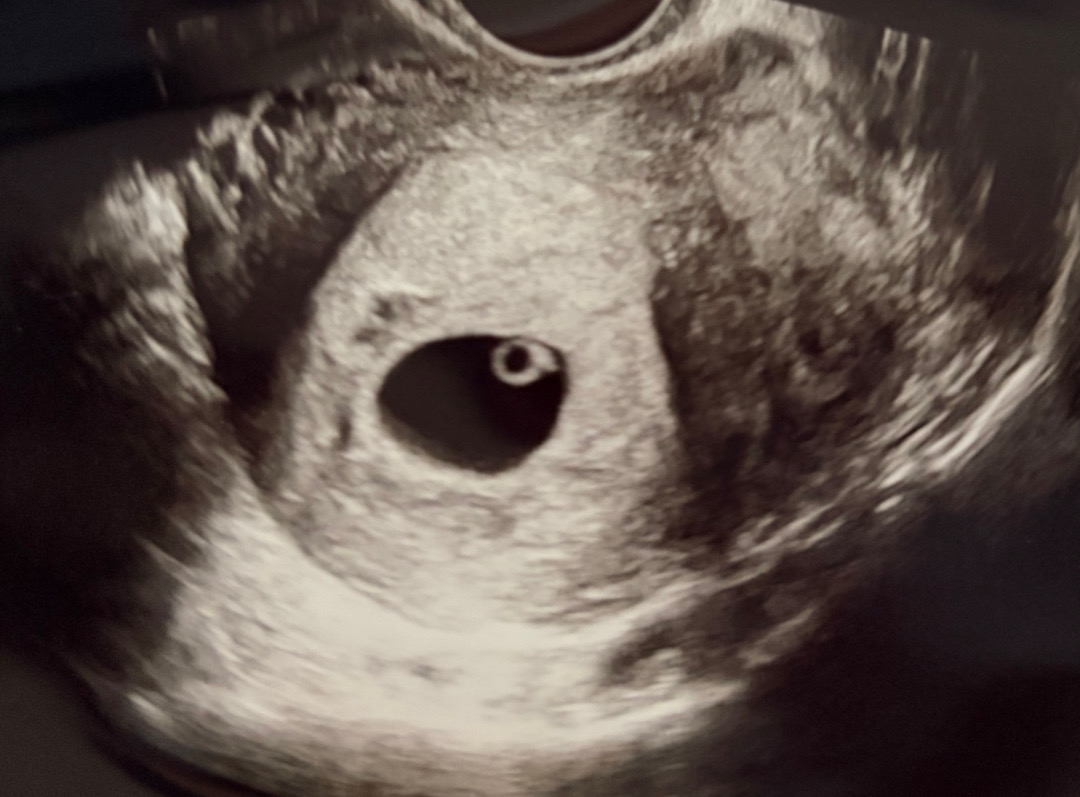

6주1일차 다이아몬드 링반지 보고왔어요! 잘 크고 있는거겠죠,,,,

동골동골 예쁘게 짓고있는 것 가타여 ,, 감사합니다

동그랗고 예뻐요🥰